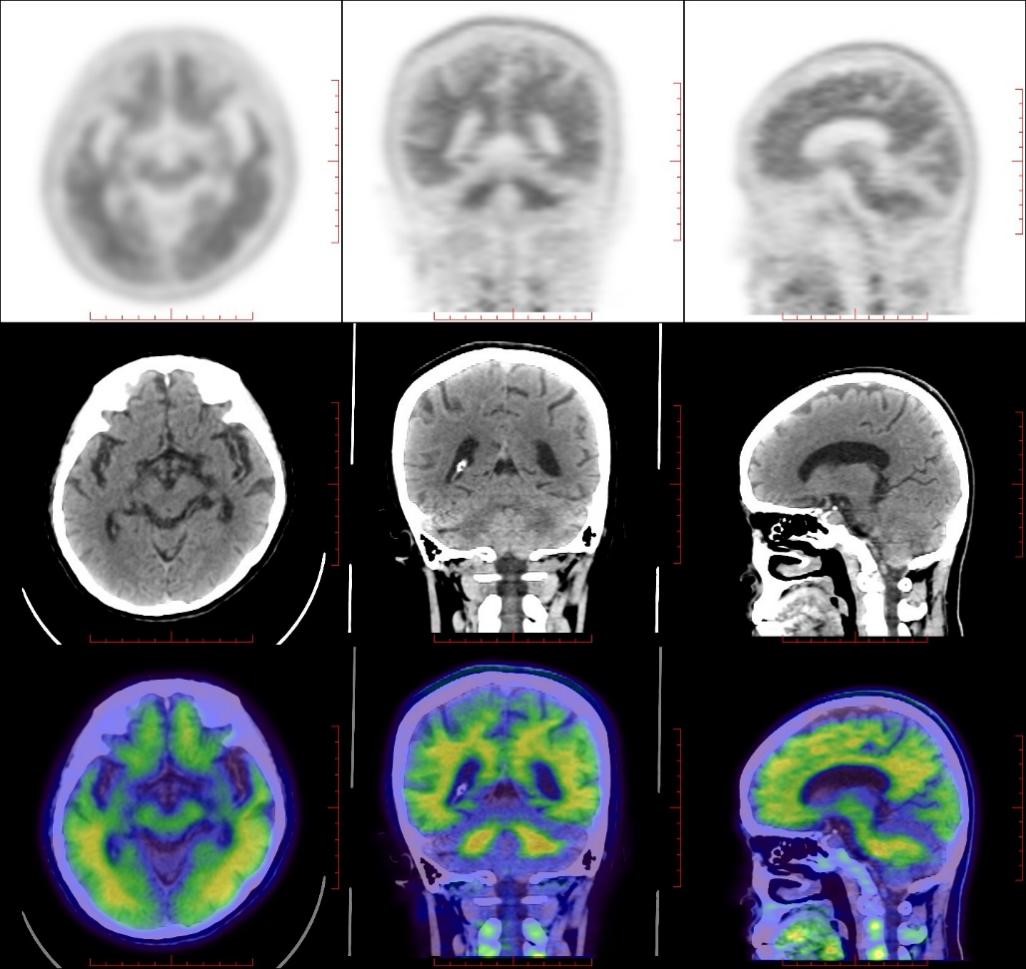

氟[¹⁸F]贝他苯Aβ-PET/CT脑显像检查阳性患者

如图,可见大脑灰质弥漫性β-淀粉样蛋白(Aβ)沉积;CT可见脑皮质萎缩。